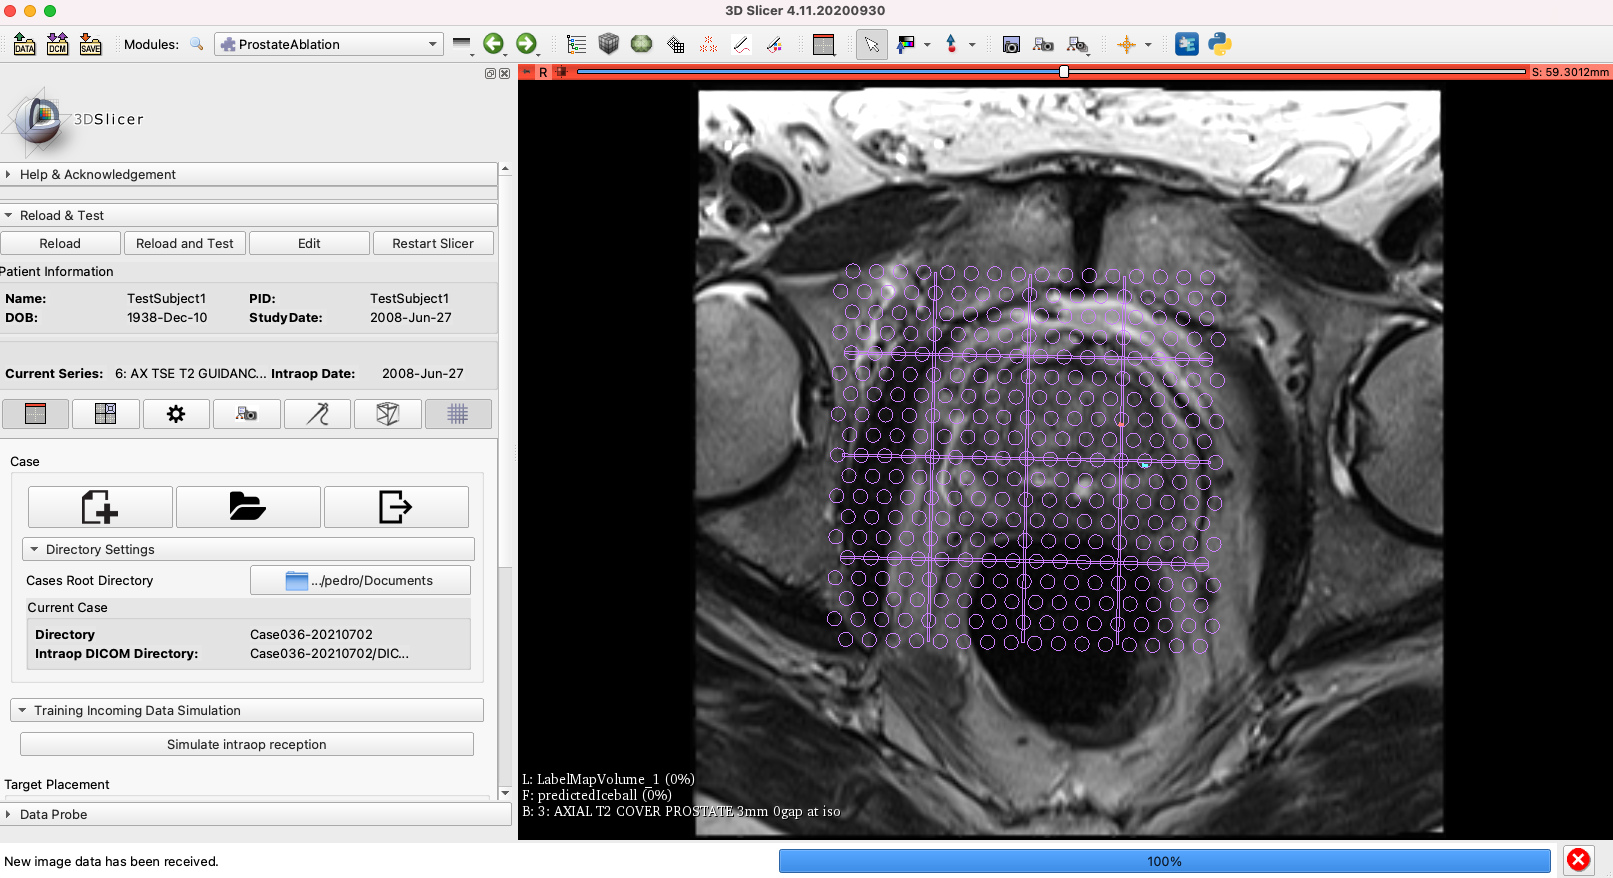

Pedro did the modifications to addapt the current module to Python3. Most of the errors were related to dict_keys and managing the markups. We also had a problem loading the DICOM files, but was fixed replacing “slicer.util.loadVolume” by “self.scalarVolumePlugin.load”. There are still some miror errors that has to be address within next week.

Figure 1: ProstateAblation module